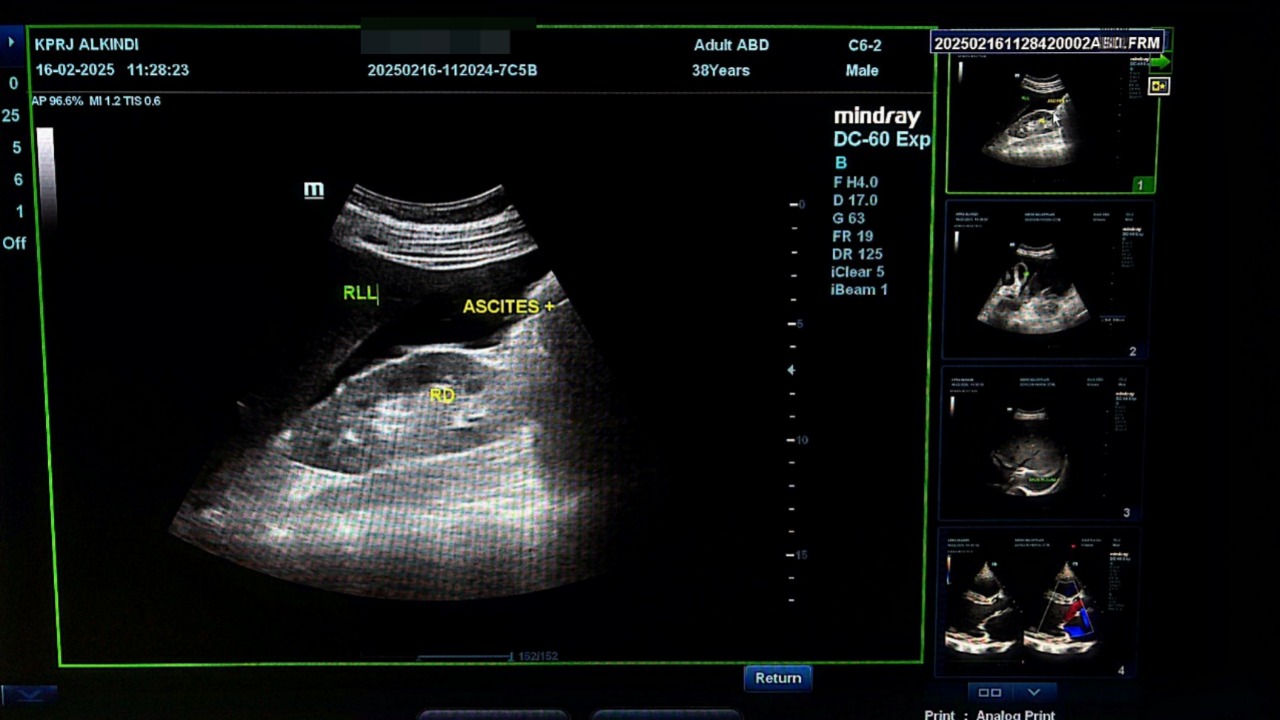

Pada pemeriksaan USG Abdomen ( 16-02-2025) didapati akumulasi cairan pada kantung paru(efusi pleura) , kantung perut( Ascites)